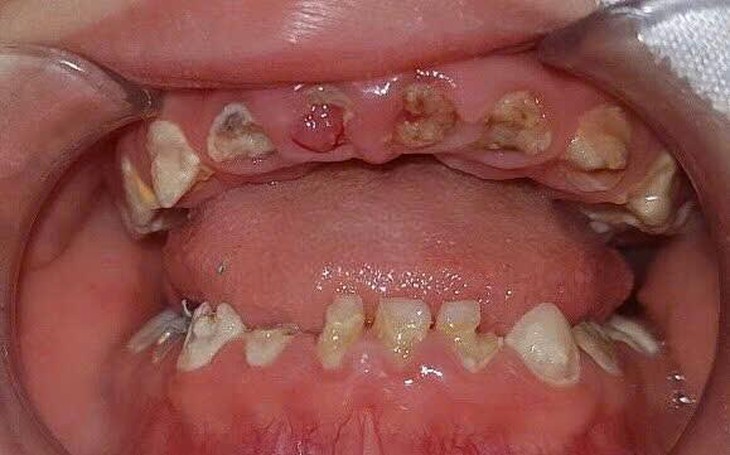

Men răng người mắc bệnh thường xốp do cấu trúc chứa nhiều thành phần sợi protein hơn là các cấu trúc khoáng hóa, điều này làm cho răng có hiện tượng vỡ men sau khi mọc. Nhiều nghiên cứu chỉ ra rằng các răng mắc bệnh rất nhạy với sâu răng, và sâu răng trên nền răng mắc kém khoáng men sẽ tiến triển rất nhanh.

Vì vậy, người bệnh thường được phát hiện ở giai đoạn muộn, tức là răng đã có hiện tượng vỡ men nhiều, làm cho người bệnh và bác sĩ nghĩ là sâu răng. Tuy nhiên, nếu răng kém khoáng được điều trị như phác đồ điều trị sâu răng thì sẽ dễ dẫn đến thất bại, nên cần phân biệt rõ sâu răng và bệnh này, sâu răng trên nền kém khoáng để có kế hoạch điều trị phù hợp.

Với các răng hàm mắc kém khoáng thể trung bình và nặng, men răng có hiện tượng vỡ men răng ngay sau khi mọc, bề mặt thường có mảng bám và có sâu răng thứ phát, khi có sâu răng thì bề mặt bị vỡ rất nhanh, việc điều trị sẽ trở nên phức tạp hơn với bác sĩ vì dán dính bị ảnh hưởng.